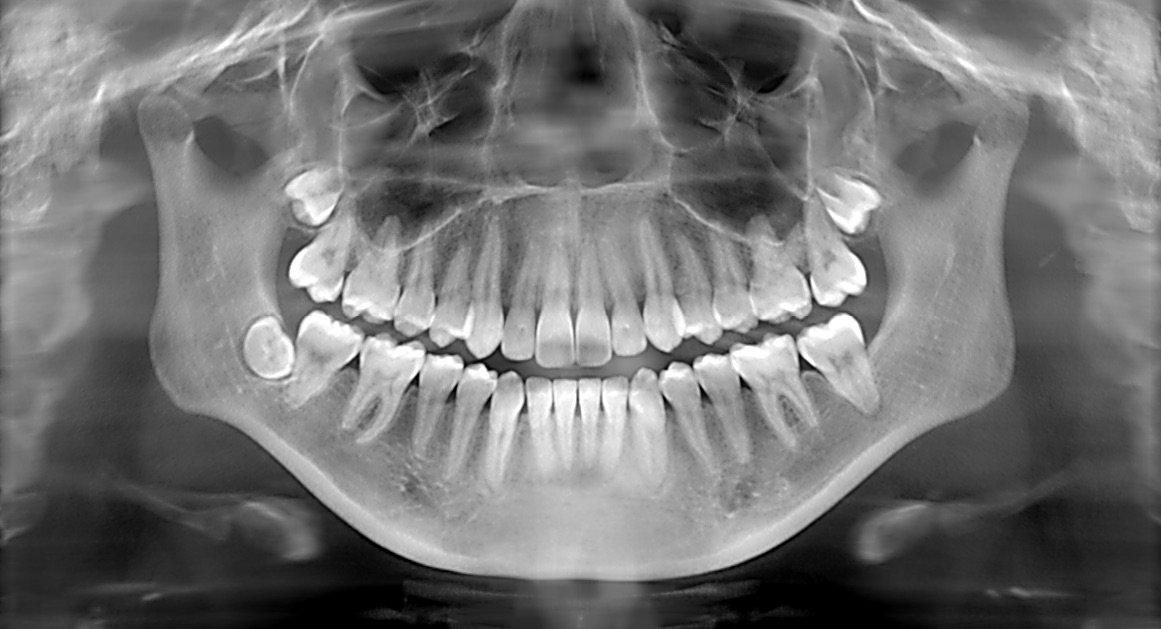

At City Smiles Dental Clinic, Rajesh was introduced to the precision diagnostics service. This advanced technology offers a comprehensive view of dental issues with unparalleled accuracy, allowing for early detection and targeted treatment plans. The X-rays revealed a hidden cavity that had reached the nerve, causing the intense pain. Without this precise diagnostic tool, the cavity might have gone unnoticed until it caused more severe damage.

Precision dental X-rays are a game-changer for individuals like Rajesh, who suffer silently due to fear of the unknown. This innovative approach not only identifies existing problems but also helps in spotting potential issues before they escalate. The peace of mind that comes from understanding the exact nature of one's dental health is invaluable.

Moreover, precision diagnostics with dental X-rays is not just about addressing immediate problems. It plays a crucial role in preventive care, helping individuals maintain optimal dental health. By detecting issues early, patients can avoid more invasive procedures and enjoy long-term savings on dental expenses.